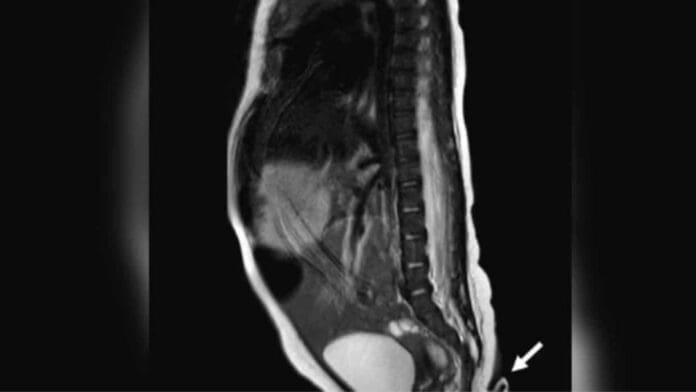

El crecimiento de esta extremidad en la parte baja de la espalda mide exactamente 5.7 centímetros y se trata del segundo hijo de la pareja, los cuales están sanos y no cuentan con ningún antecedente de este tipo de malformaciones.

De acuerdo a testimonios, la cola sobresale del coxis del pequeño y la punta es más estrecha que la base, en este sentido, los médicos pincharon al bebé para verificar si tenía movimiento, pero no fue así por lo que el bebé solo lloró tras el pinchazo.

Cabe destacar que tras cumplir dos meses, la cola creció tres pulgadas, por lo que tuvieron que extirparla en una operación sencilla y post extirpación notaron que estaba compuesta de tejido blando, venas y arterias.